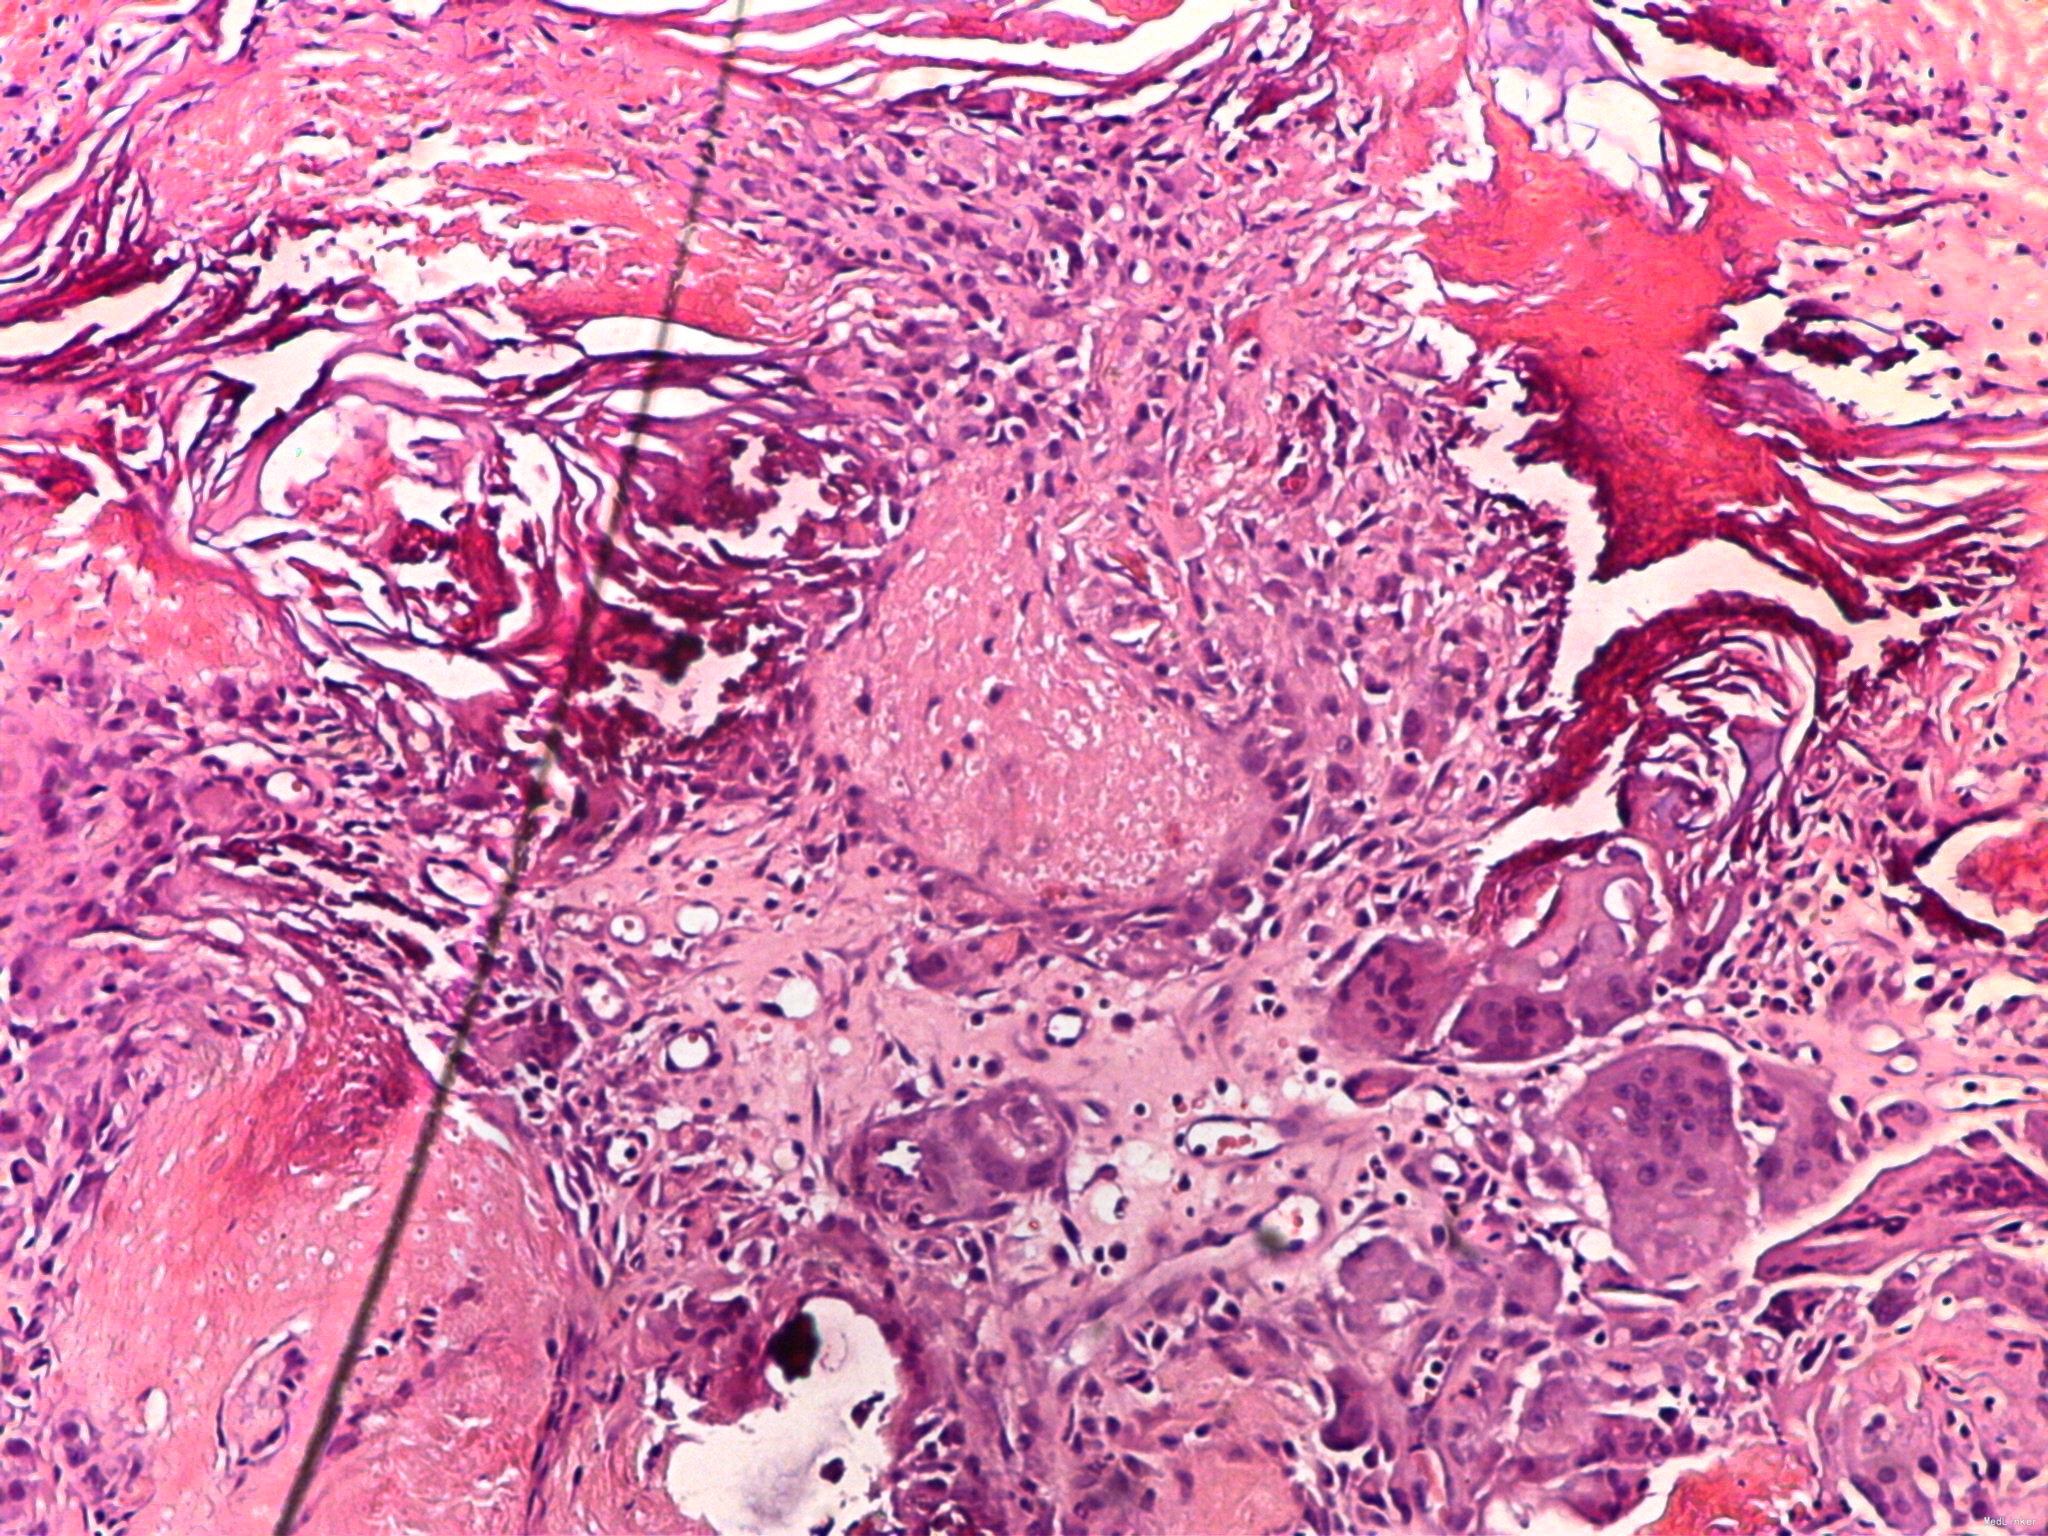

病理检查示:皮下囊肿.囊壁内见嗜碱细胞、影子细胞及钙化区

诊断:钙化上皮瘤。

钙化上皮瘤临床相对比较常见,儿童多发,其临床表现有时和表皮囊肿不易区分,病理见影子细胞可以确诊